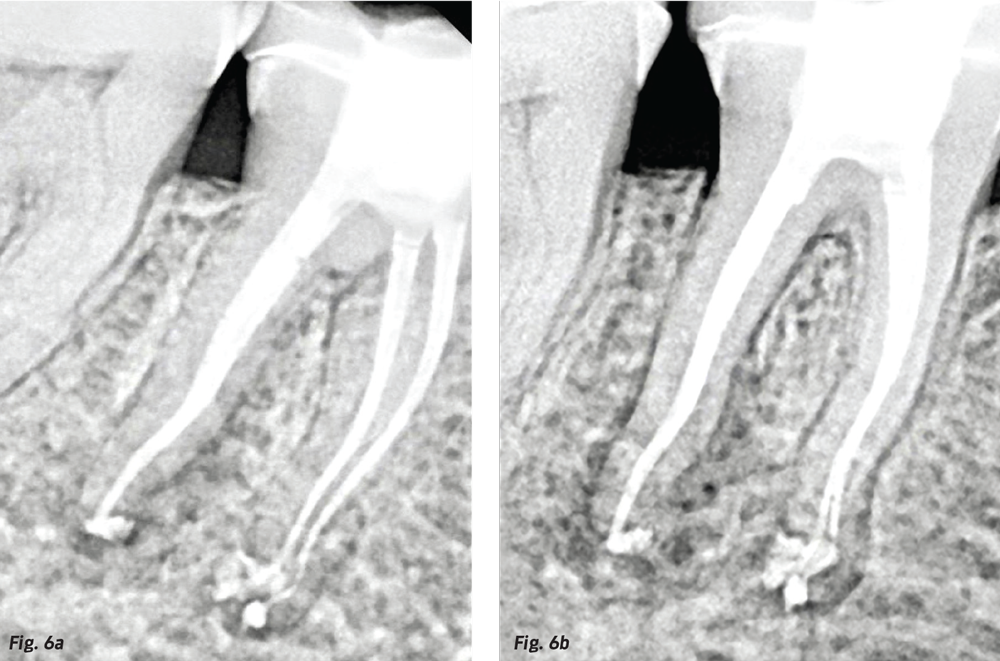

Fig. 5a: Master gutta percha points cemented in canals with BC HiFlow Sealer. Note the short apical lateral canals filled just by cementing a single gutta percha cone in the palatal root; also note the incomplete lateral fill of the MB root complex (left). Fig. 5b: Continuous wave electric heat plugger in its final position after a modified CW downpack to midroot. Note the MB2 and MB3 complexities filled by bioceramic sealer after the shortened hydraulic wave of condensation (right).

How does this simplify warm gutta percha obturation? Primarily by shortening the required downpack distance into the canal. As mentioned above, with the no-net-shrinkage of bioceramic sealers, the warmed gutta percha and the sealer beneath it need just half the previous depth of continuous wave downpack to move sealer into the full apical and lateral extents of root canal systems (Figs. 5a and 5b, p. 74). The shortening of the downpack means that pluggers no longer need to be prefitted in canals before cementation of the master cone, and it also means that backfilling can be done with a small squirt of GP from a backfill syringe—or, better yet, with a sealer-coated backfill cone (Autofit Backfill Gutta Percha, Kerr Endodontics).